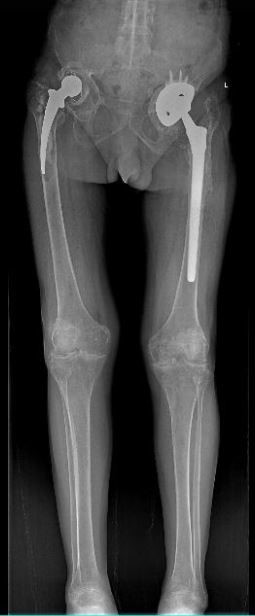

男 70岁

双侧股骨头置换术后

双侧股骨头置换术后复查

通过全景拼接图像可以清晰显示双下肢对比情况,为术后评估提供更多影像学资料。